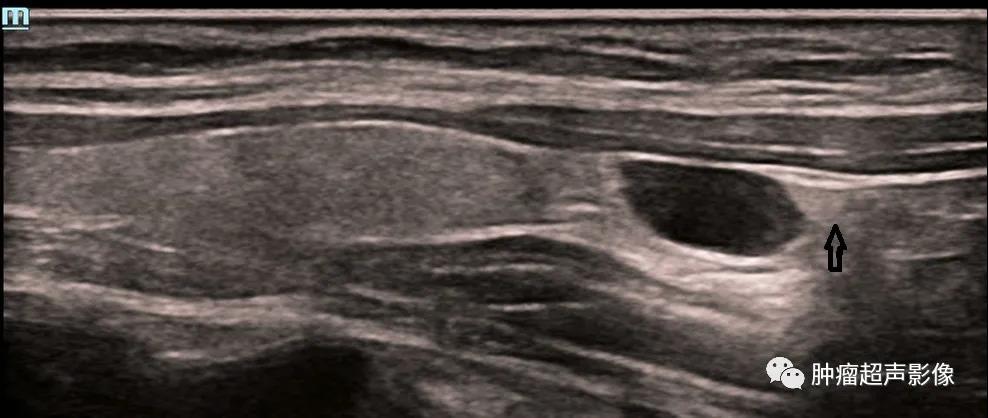

甲状腺左侧叶下极旁见边界清的无回声,椭圆形,与甲状腺组织之间有高回声包膜分隔,囊壁薄而光滑,透声佳,无血流,上极侧可见残留的高回声甲状旁腺(箭头示)从而确定甲状旁腺囊肿。